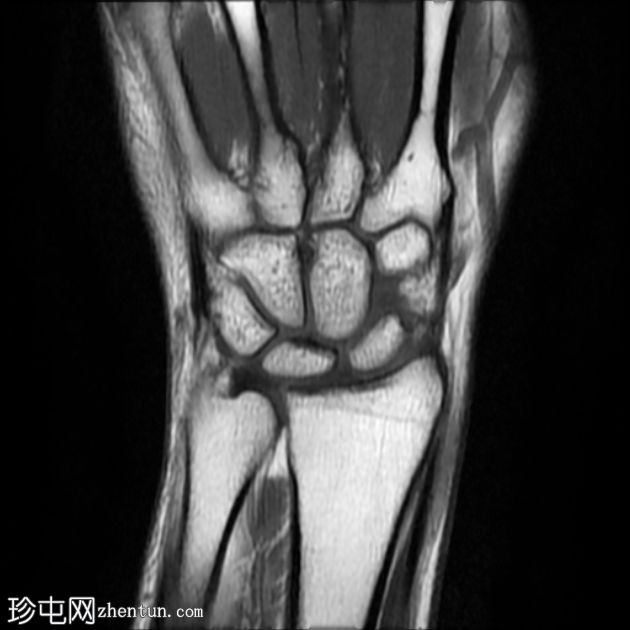

MRI

冠状位

T2加权像

T1加权像

腕背多房性腱鞘囊肿(轴位、矢状位和冠状位图像均可见),位于伸肌腱下方的腕背关节囊内,提示为腕背腱鞘囊肿。

该病例展现了腕背腱鞘囊肿的典型

影像

学表现和位置。